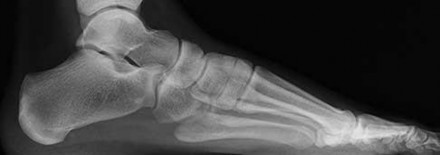

QUESTION 4

of 100

Figures 4a through 4j

1

- Normal foot

Figures 4a through 4j do not show any signs of a coalition.